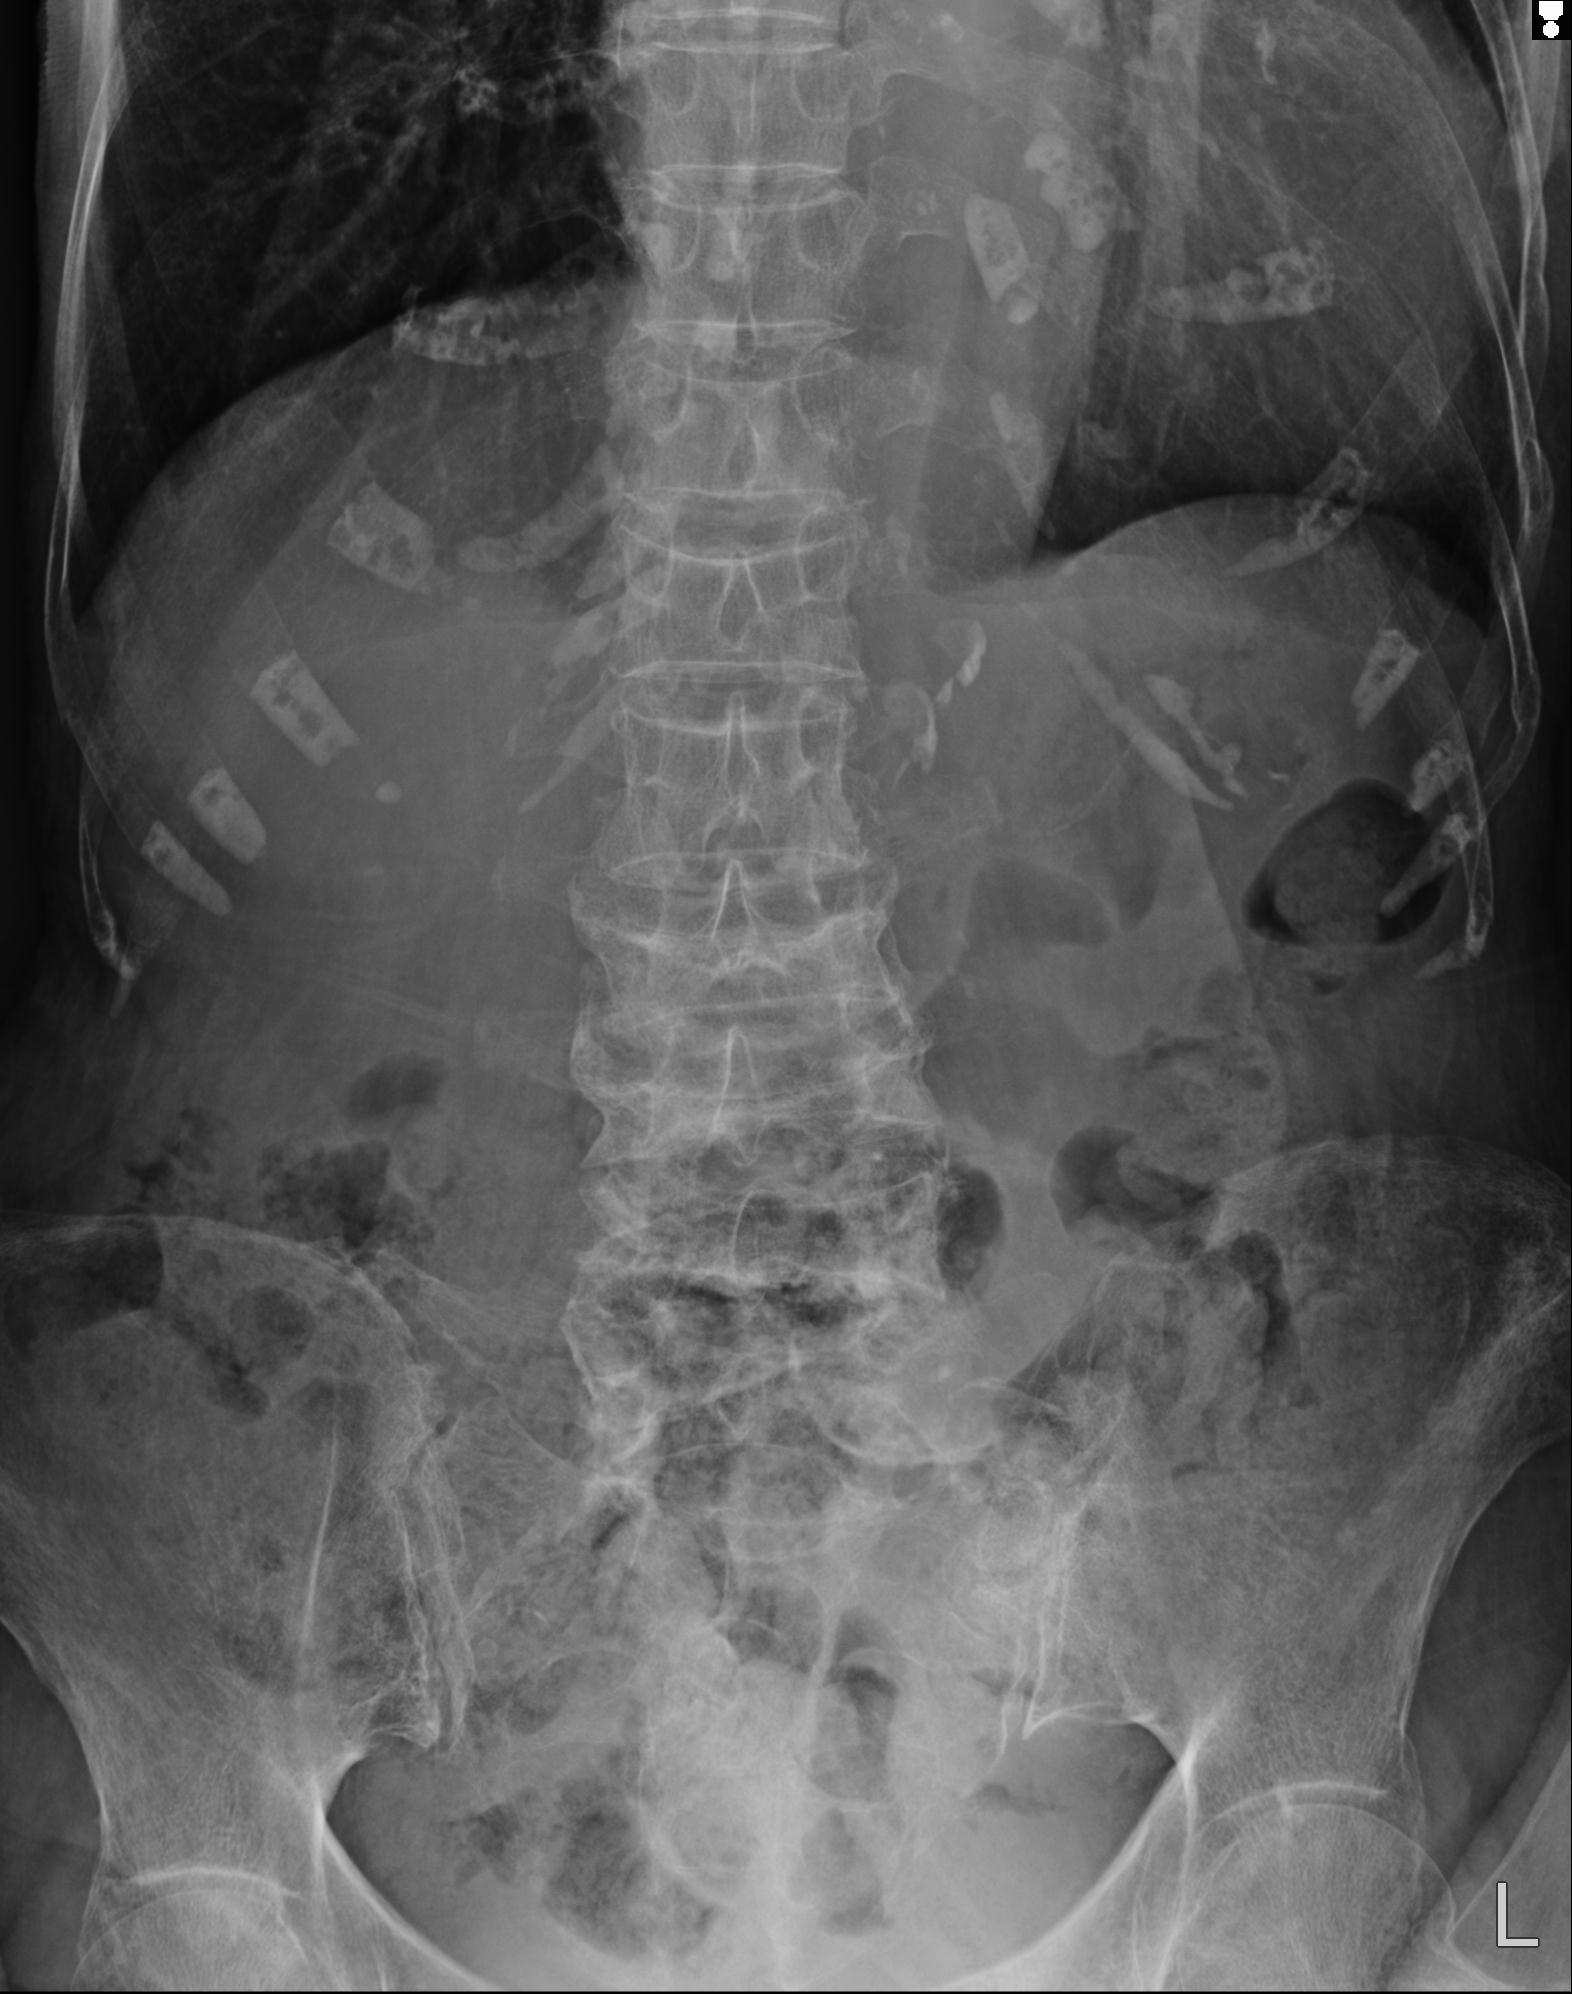

102916 2/1 と 3/22 腰椎 2R 74歳女性 LIFX

93804 2/9 腰椎 2R 後方固定 67歳女性